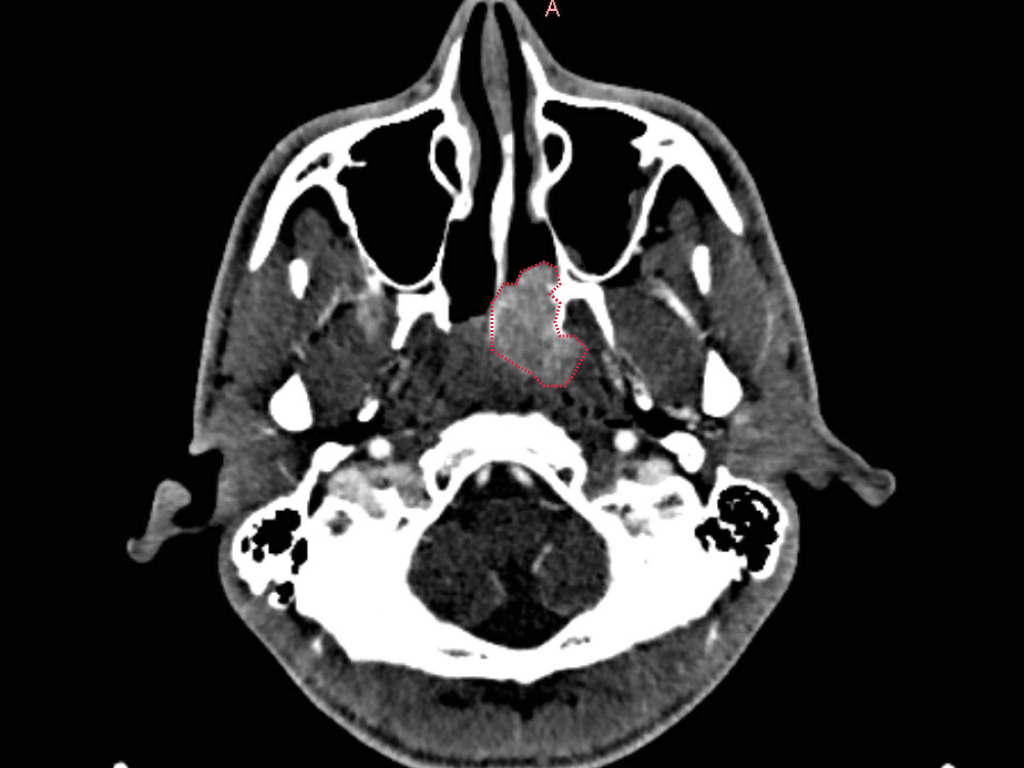

Ортодонт увидел на снимке пациента изменения в носоглотке и клиновидной пазухе. Он не стал ставить диагноз, но сразу направил пациента к ЛОР-врачу.

На МРТ видно образование - ювенильная ангиофиброма носоглотки

Я диагностировал новообразование - доброкачественное, но требующее срочной операции. Спустя 2 месяца мы прооперировали пациента, прошёл год, и сейчас - стабильная ремиссия. Это стало возможным только благодаря внимательности стоматолога.

КТ после удаления новообразования